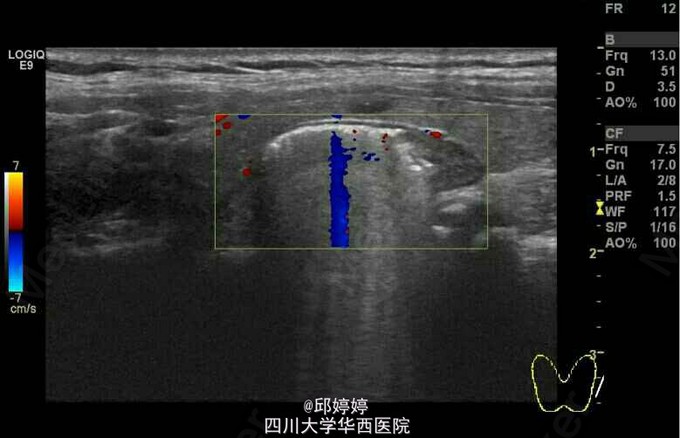

患者,女,60岁,无特殊不适,行常规体检。超声检查发现患者颈部甲状腺左侧叶后方查见大小约23x9mm的杂乱回声团,内可见气体样强回声,后方回声衰减(图1-3)。 诊断:食管憩室。 此种现象较为少见,应注意与甲状腺本身的病变相区别,以防误行进一步的穿刺活检而导致食管损伤。